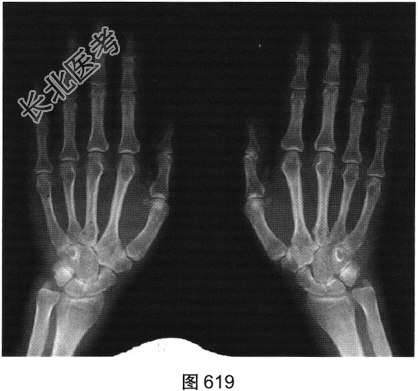

- 简答题2、患者行双手X线及MRI检查,见图619~图622。请问X线平片及MRI图像有哪些阳性表现?